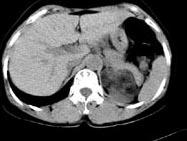

问题 男性,28岁,左腰背酸胀5个月,CT检查如图所示,应诊断为 ( )

选项 A、左肾上腺腺瘤 B、左肾上腺转移瘤 C、左肾上腺错构瘤 D、左肾上腺嗜铬细胞瘤 E、左肾上腺髓样脂肪瘤

答案 C